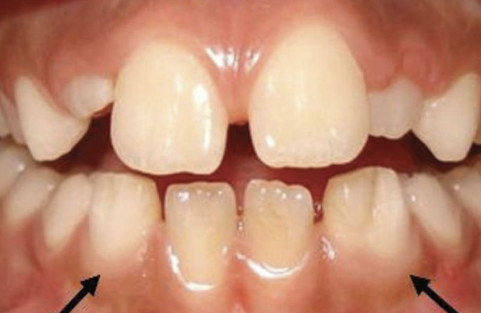

enamel can be white, yellow, brown, and or have different degrees of hypoplasia; most commonly in bicuspid because of their relation ship with the deciduous molars; causes fever, PA inflammatory disease of overlying deciduous tooth, trauma

turner’s hypoplasia